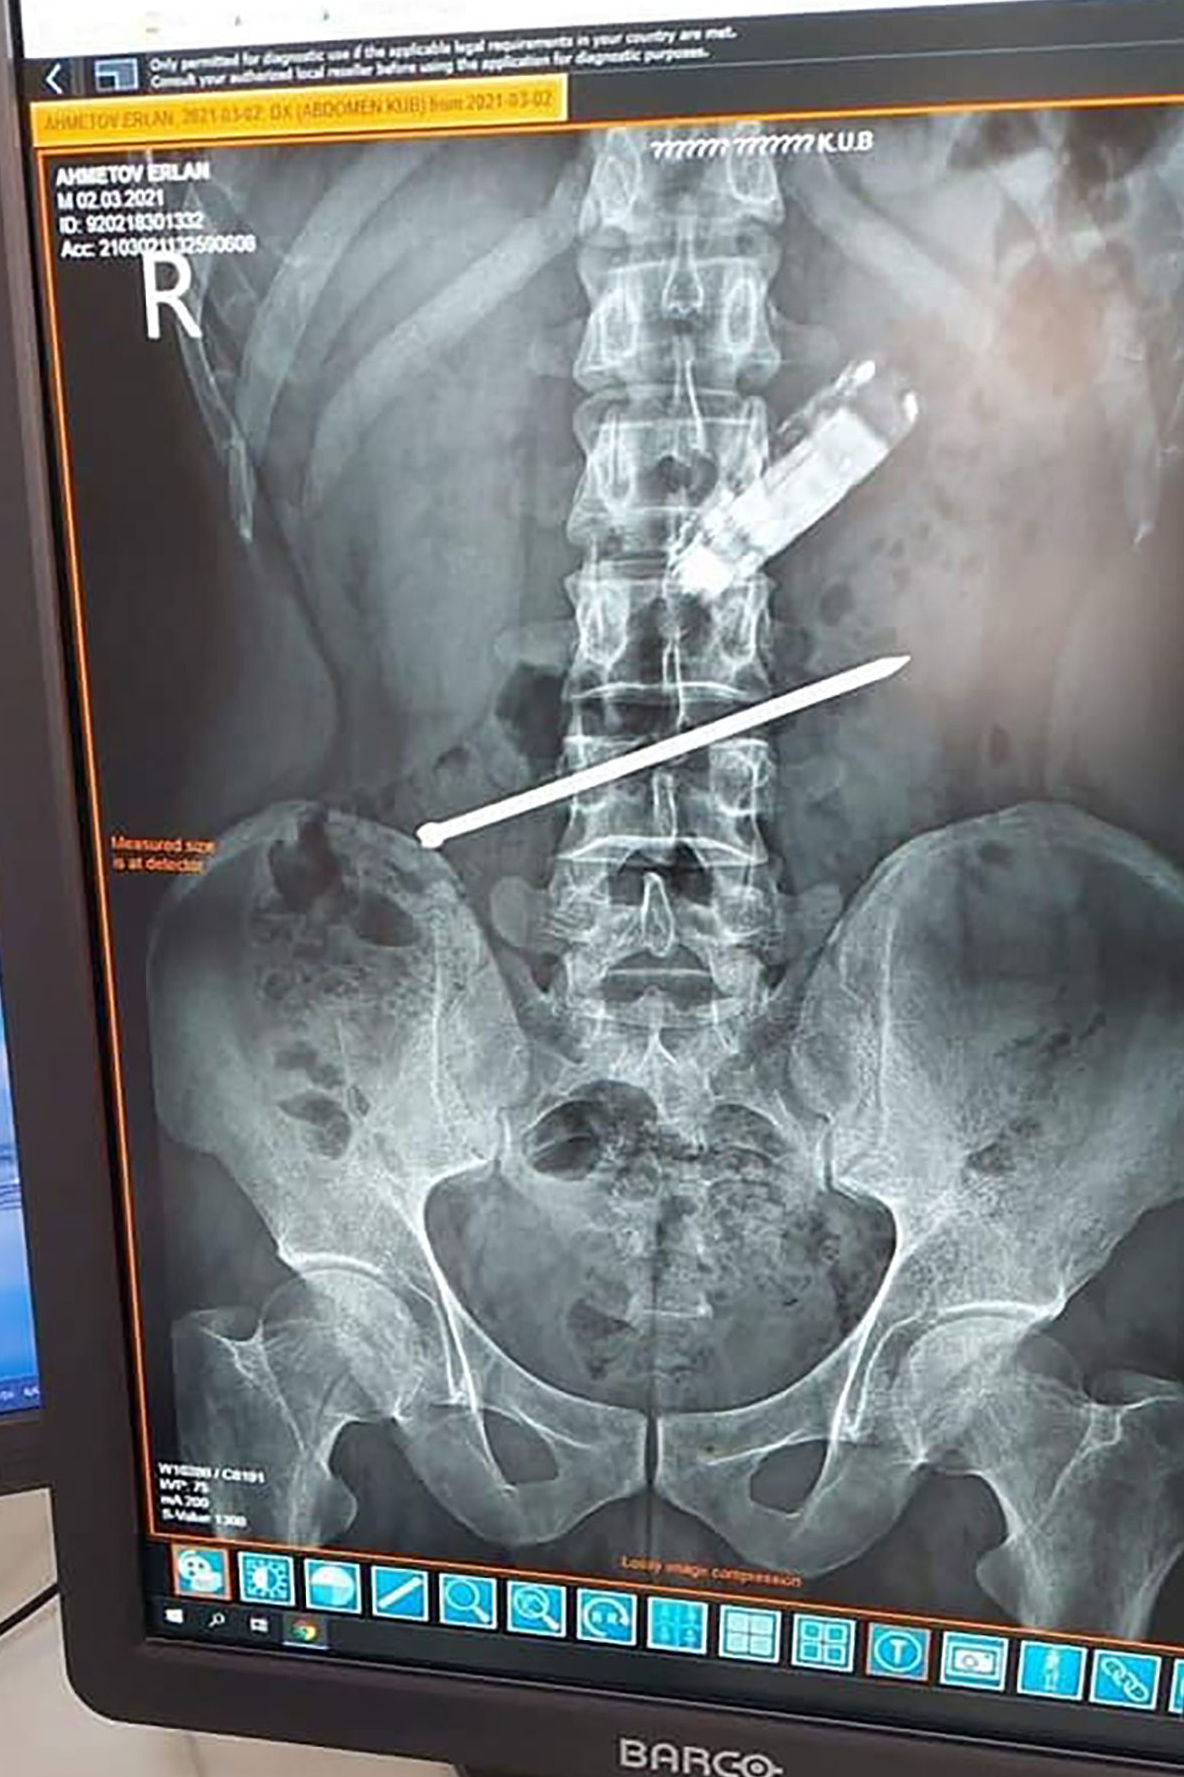

"Көпсалалы облыстық ауруханаға түскен ер адамның айтуынша, ол шамамен 8 сағат бұрын ұялы телефонды жұтып қойған", - делінген хабарламада.Ер адамға жедел түрде іш қуысы органдарының рентгенографиясы жасалды, одан бөтен дене: ұялы телефон мен шеге табылды.

"Телефонның батареясы өте қауіпті, ол кез келген уақытта асқазанның шырышты қабығын күйдіруі мүмкін. Мамандардың кеңесінен кейін икемді эндоскоптың көмегімен бөгде зат сәтті алынып тасталды. Оны эндоскопист дәрігер Айбек Ақбаев жасады", - деді облыстық денсаулық сақтау басқармасы.Ер адамның неліктен мұндай әрекетке барғаны айтылмады.